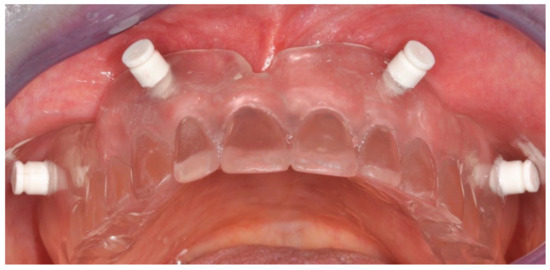

Figure 4.

Interim prosthesis without cantilevers.

Figure 5.

Interim prosthesis after implant placement.